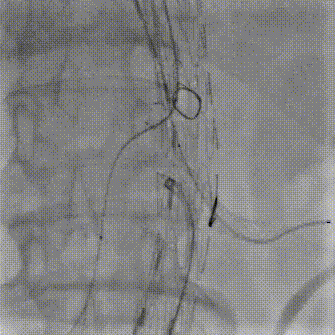

病史:68岁男性,胸腹主动脉夹层动脉瘤三年余,2021年接受B型夹层腔内修复术,术后恢复良好。近期复查发现腹主动脉夹层破口增大,假腔扩张明显。

手术方案:内脏区体外三开窗(CA、SMA、LRA),RRA原位开窗。

预三开窗+右肾原位开窗重建

Fustar+Futhrough原位穿刺破膜

预三开窗+肾动脉原位开窗重建